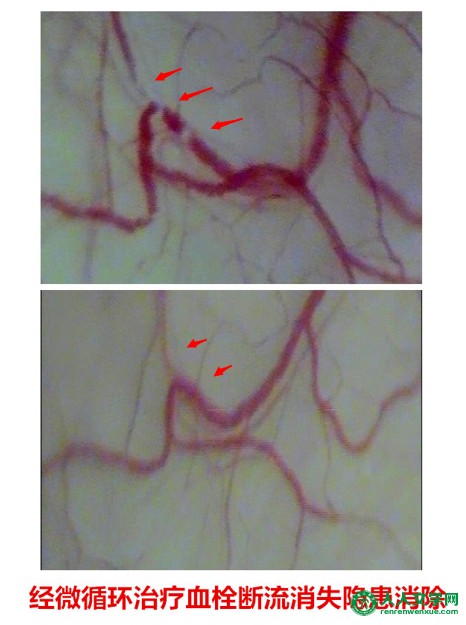

(2.)预防脑梗塞和心肌梗塞:脑梗塞和心肌梗塞之前,微循环检查可以发现“白色微小血栓”,大量的“白色微小血栓”是造成脑梗塞和心肌梗塞的病理基础,提前发现和治疗“白色微小血栓”是预防脑梗塞和心肌梗塞的最佳措施!